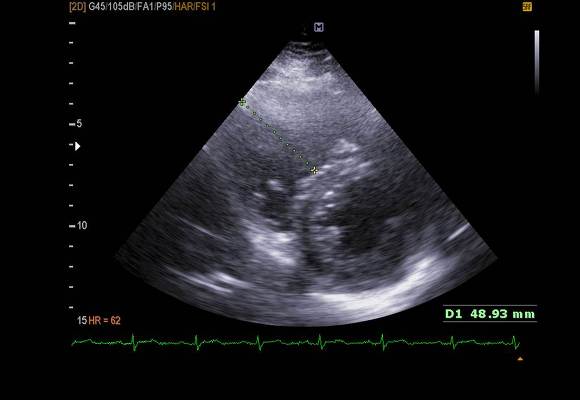

pic 7. RV enlarged

pic 3. PSX - systole 시 septum이 flattening 해짐.

LV 빼고 다른 챔버 모두 enlargement 있었고.

pulmonary hypertension 으로 인해 D-shape  보였습니다.

이로 인해  특히 septum 쪽 wall motion 이 떨어져 있었습니다.